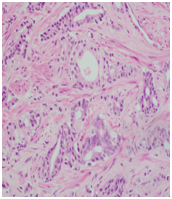

Trans-rectal ultrasound guided biopsy of the prostate confirmed the adenocarcinoma Gleason score 9 (4+5), while the mandibular lesion biopsy revealed metastatic prostate adenocarcinoma (Figures 6–8).

Figure 6 Mandibular biopsy.